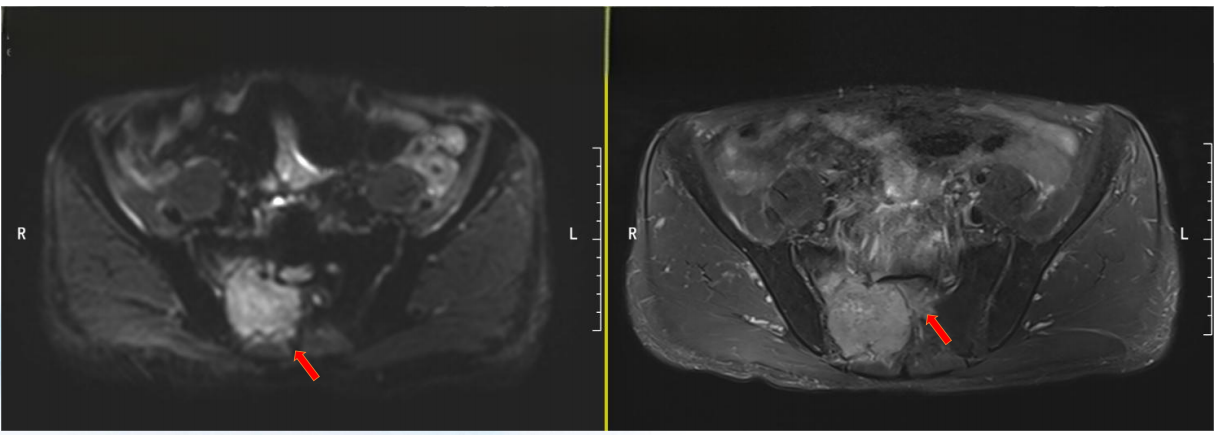

直肠MRI(2020年3月25日)提示直肠中上段壁增厚,考虑直肠Ca(图1)。

图1. 直肠MRI(2020年3月25日)